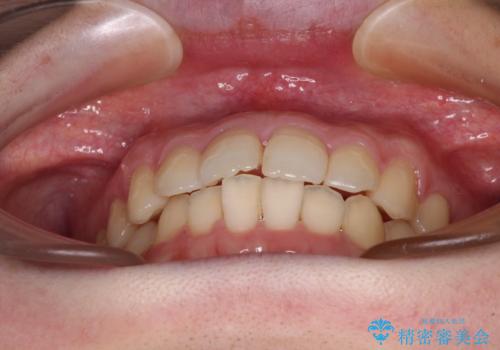

デコボコ歯列をきれいに インビザラインによる矯正治療

- 上下歯列全体のデコボコを気にして来院された患者様です。

主に下顎歯列全体の後方移動とIPR(歯と歯の間を削る)によってデコボコが解消するように設計し、インビザラインにより治療を行うこととしました。

1年半程度で終了するのではないかと予想しましたが、途中1年以上の来院がなく、トータルで3年の時間がかかってしまいました。

前歯のデコボコはより改善することが望ましい状態でしたが、患者様の希望により終了することとなりました。